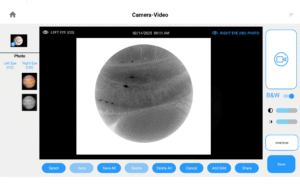

Opteon™ Slit Lamp Imaging + Meibography

Photos & Videos. Clinical Documentation. Patient Education. Reimbursement.